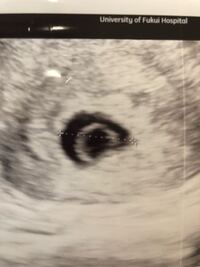

妊娠7週目で心拍が確認ができないと流産? 心拍確認とつわり・出血は関係はない 心拍確認ができないのにつわりや出血がある場合、だからといってら=無事妊娠中、というわけではありません。 妊娠初期の流産の確率 ここに 「稽留流産の診断から一転して心拍を確認できた体験談」をまとめ ました。 心拍確認後も、無事に出産されています。 なので、 稽留流産の診断を受けても、手術までは、妊娠継続の可能性はゼロではありません 。 ︎ 稽留流産と診察された

7週目 心拍確認できない 出産- 一般的に胎児心拍が確認できた後の流産率は3~12%と推定されていますが、実は論文報告が少なく結論がばらけています。何個かの報告をご紹介させていただきます。 ≪論文紹介≫ ①症状の全くない心拍確認できた後の流産率 Tong S, et al Obstet Gynecol 08 (結論)妊娠7週で心拍確認できない=100%流産ではない。ただし、条件あり この調査に限って言えば、 妊娠7週中に心拍が確認できなくても自然妊娠なら過度に心配する必要はないが、体外受精の場合は100%妊娠継続の可能性はないと思った方が良い 、という結論に至りました。

7週目 心拍確認できない 働くナース ぺぇの流産 妊娠 出産ブログ 7週目 心拍 確認 できないこのワードを帰ってから何度もネットで検索しました。だいたい、7週目に入っていれば、心拍は確認できるということばかり書いておりあぁや 経膣超音波法の場合は、4週目頃まで、6週目頃まで胎芽の心拍が確認できないことがあります。 それ以降は確認できることが殆どです。 胎芽確認後の流産の確率は? 胎芽を確認でき、心拍を確認できた後に流産をしてしまう確率としては約15%あります。